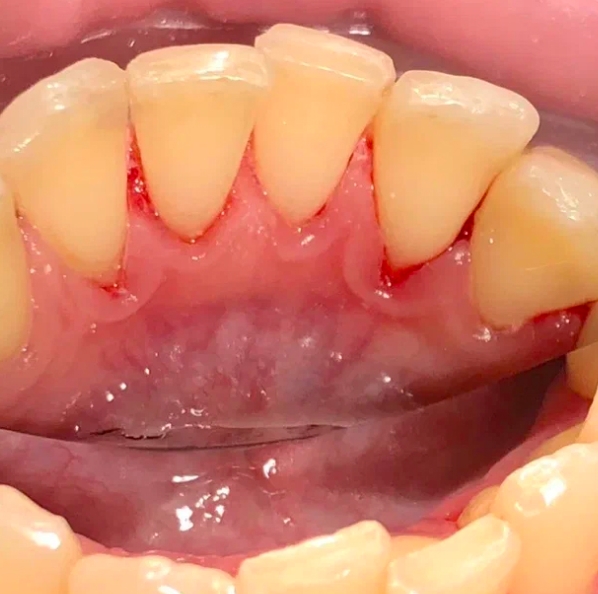

До и после лечения

В «Стоматологию Комфорта» обратился пациент с жалобами на наличие зубных отложений, а также кровоточивость дёсен во время чистки зубов. Врач Луцюк Наталья Владимировна провела осмотр и диагностировала хронический катаральный генерализованный гингивит. Было принято решение о проведении профессиональной гигиены полости рта с целью снятия минерализованных зубных отложений ультразвуком и удаления пигментированного налета пескоструйным аппаратом, а также последующей полировкой щеткой с пастой SuperPolish.

В ходе лечения проведены следующие работы:

- снятие минерализованных зубных отложений ультразвуком;

- удаление пигментированного налёта пескоструйным аппаратом;

- полировка зубов резиновой насадкой;

- финальная полировка пастой SuperPolish.